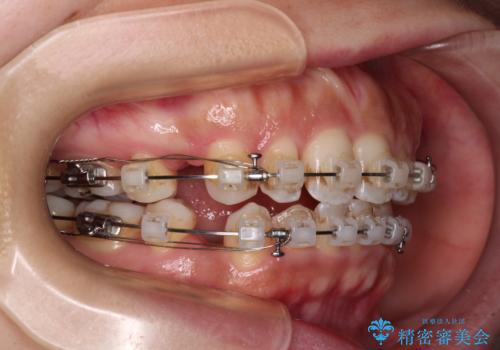

唇が閉じにくい ワイヤー装置での抜歯矯正

- 矯正装置

- クリアブラケット

- 治療期間

- 1年11ヶ月

上下ともに前歯が少し舌側に傾斜したような仕上がりとなりましたが、口が閉じやすくなったとのことで、患者様には大変満足していただけました。